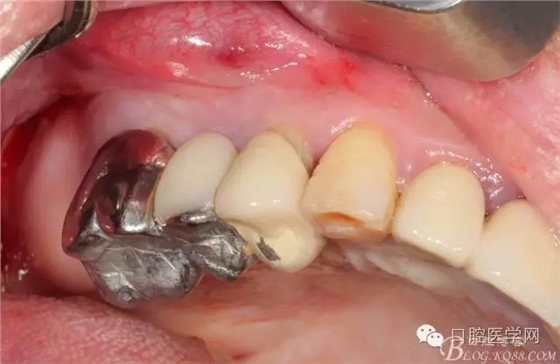

牙周治療以后過了段時間我們開始拔牙種牙,上圖是牙周治療以后開始種牙的口內(nèi)照片,效果還是有的。

拔掉以后(這樣能夠整體拔出 說明這組牙是非常松動了)

拔牙以后 拔牙窩少許肉芽 發(fā)現(xiàn)13遠(yuǎn)中還是有些肉芽的

簡單清理以后 (一般這種情況我是不太翻瓣的)這個患者我在清理13遠(yuǎn)中時候我發(fā)現(xiàn)有些肉芽而且超過了我的預(yù)期的量,我開始不太淡定了 。 我在想牙周科同事是不是知道我要拔牙,沒有在14 16 牙位用洪荒之力刮治啊。結(jié)果我翻瓣一點點去檢驗了下牙周科刮治的效果,那么結(jié)果是非常好,沒啥太多的肉芽,不翻瓣完全可以刮干凈,看來我得信任我的同事啊,牙周科非常給力。13牙位遠(yuǎn)中的肉芽估計的確不好刮掉,所以留給我刮了吧。